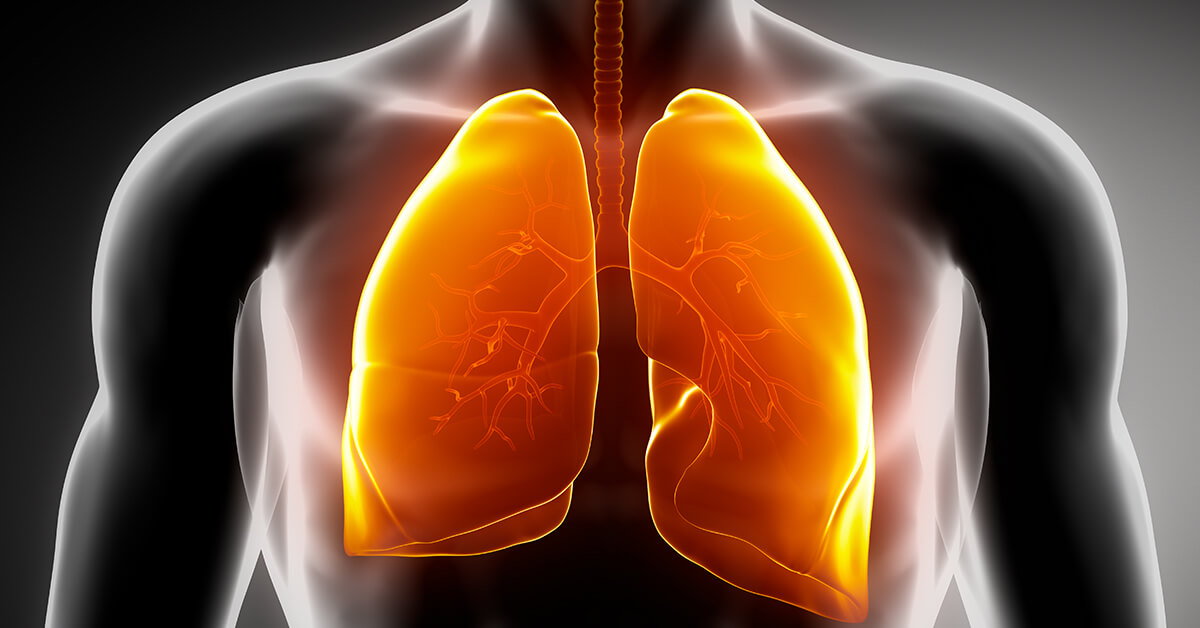

Blog: Αναπνευστικό σύστημα